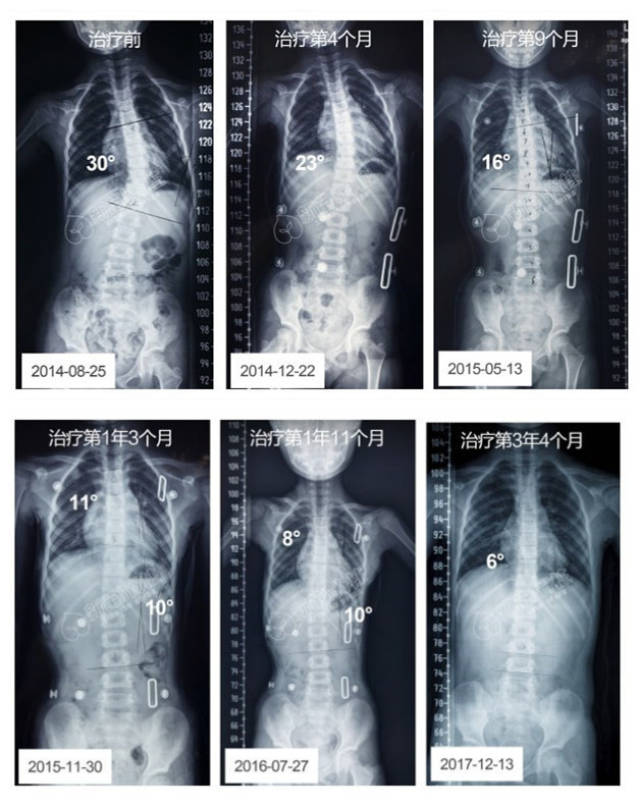

杨教授最大的幸福 | 侧弯30度女孩坚持保守治疗的故事

病例:15岁脊柱侧弯女孩经1年努力治疗,基本完全恢复!